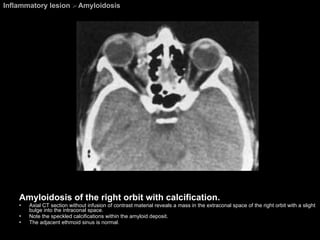

Amyloidosis On CT, amyloid deposits (homogeneous eosinophilic protein) simulate pseudotumors, vascular malformation, and other mass lesions, and the deposits can  occasionally calcify . On MR imaging, the amyloid deposits have signal intensities similar to those of skeletal muscle on all imaging sequences.

Inflammatory lesion  >  Amyloidosis Amyloidosis of the right orbit with calcification. Axial CT section without infusion of contrast material reveals a mass in the extraconal space of the right orbit with a slight bulge into the intraconal space.  Note the speckled calcifications within the amyloid deposit.  The adjacent ethmoid sinus is normal.